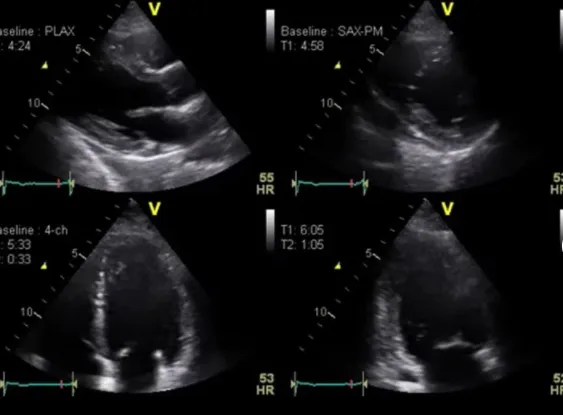

Клинические изображения

GE HealthCare Vivid T9 — универсальная ультразвуковая система для кардиологических и общих исследований у взрослых и детей, с расширенными возможностями диагностики в акушерстве и гинекологии, ангиологии, урологии, исследовании органов брюшной полости, малых органов, поверхностных структур и мышечно-скелетной системы, урологии, транскраниальных и чреспищеводных исследованиях. Ультразвуковая система среднего класса Vivid T9 объединяет признанное качество визуализации в кардиологии, характерное для линейки Vivid, и возможности широкого использования в общей диагностике, которыми отличается линейка LOGIQ.

GE HealthCare Vivid T9 поддерживает широкий спектр датчиков, включая специализированные кардиологические и обще-диагностические модели. Функции Speckle Tracking, AutoEF и Strain Imaging позволяют детально оценивать деформацию миокарда, а режимы 2D, M-Mode и допплерография обеспечивают комплексный анализ сердечно-сосудистой системы. Благодаря эргономичному дизайну и продуманному интерфейсу аппарат удобен в использовании

Кардиология

- Эхокардиография для оценки структуры и функции сердца.

- Диагностика пороков сердца, кардиомиопатий, перикардитов.

- Исследование кровотока с помощью допплерографии.